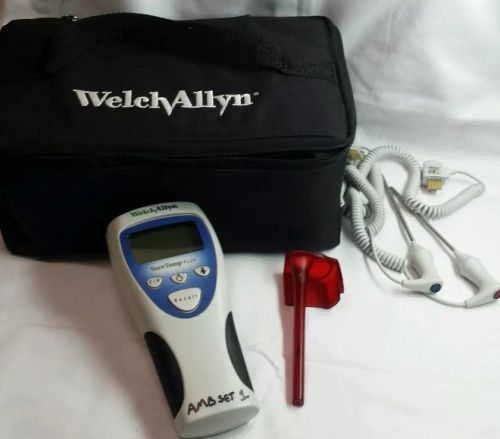

US $1,275.00

| Condition | Used

An item that has been used previously. The item may have some signs of cosmetic wear, but is fully operational and functions as intended. This item may be a floor model or store return that has been used. See the seller’s listing for full details and description of any imperfections.

| Seller Notes | “Please see test images.” |

WELCH ALLYN Sure Temp Plus Thermometer Kit 690&692 Oral Rectal Probe w/o Covers